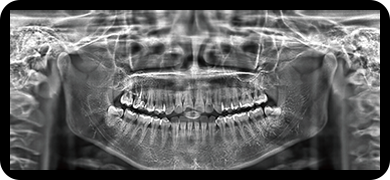

临床样片